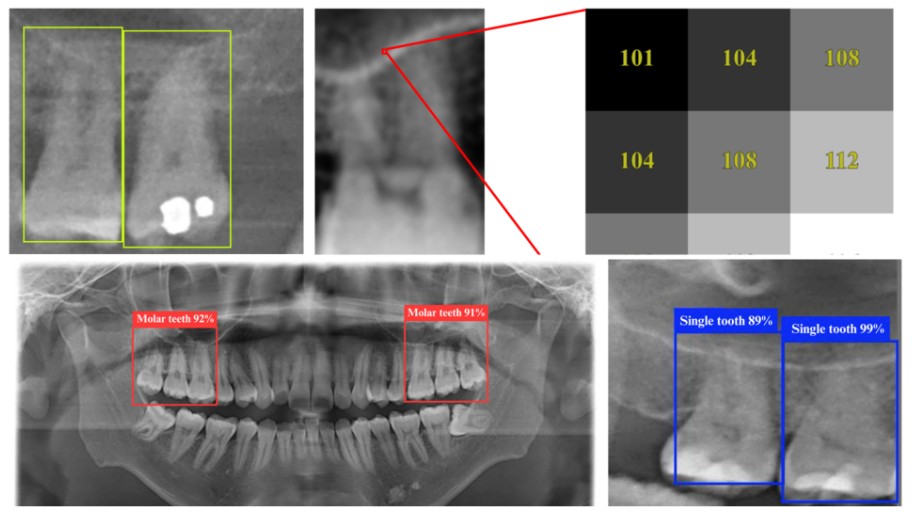

Ateneo, Taiwanese researchers develop highly accurate AI dental assistant

“The YOLO (You Only Look Once) 11n model seeks to lower the radiation exposure of patients and to reduce diagnostic costs.”